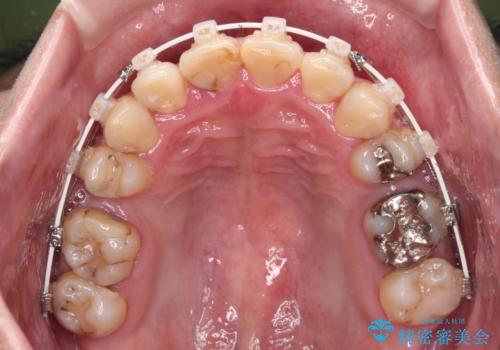

- 矯正装置

- 審美装置

第二小臼歯抜歯の矯正治療は、治療期間が長引くことが多いですが、動きが非常に良く、予定の治療期間で終えることができました。

上下の正中も思っていた以上に良い位置に改善されました。